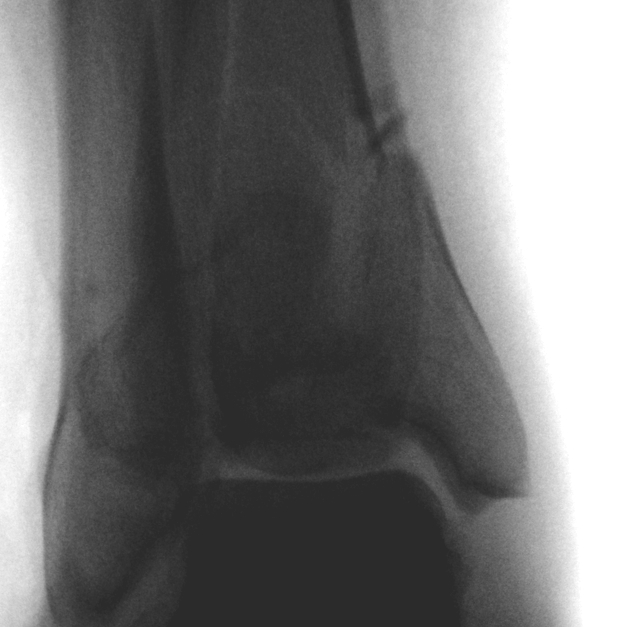

Tibial Plafond Pre External Fixator APTibial Plafond Pre External Fixator LateralTibial Plafond Post External Fixator APTibial Plafond Post External Fixator Lateral